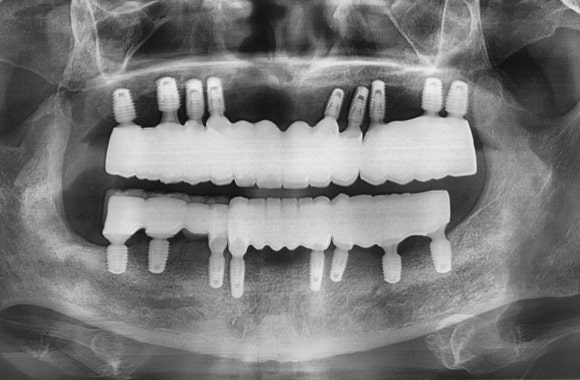

이해를 돕기 위한 예시 사진입니다.